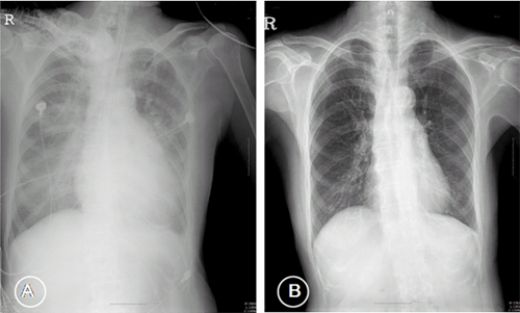

Bu belirtiler, hastanın genel sağlık durumuna ve kanamanın şiddetine göre farklılık gösterebilir. Özellikle kanlı balgam ve nefes darlığı gibi belirtiler, acil müdahale gerektiren durumlar arasında yer almaktadır. Tanı Yöntemleri Akciğerde kılcal damar kanamasının tanısı, hastanın semptomlarına ve fizik muayenesine dayanarak konulmaktadır. Tanı sürecinde kullanılan yöntemler arasında şunlar bulunmaktadır:

Bu yöntemler, akciğerde kanamanın kaynağını belirlemek ve olası komplikasyonları değerlendirmek amacıyla kullanılmaktadır. Tedavi Yöntemleri Akciğerde kılcal damar kanamasının tedavi yöntemleri, kanamanın nedenine, süresine ve hastanın genel sağlık durumuna bağlı olarak değişiklik göstermektedir. Tedavi seçenekleri arasında: